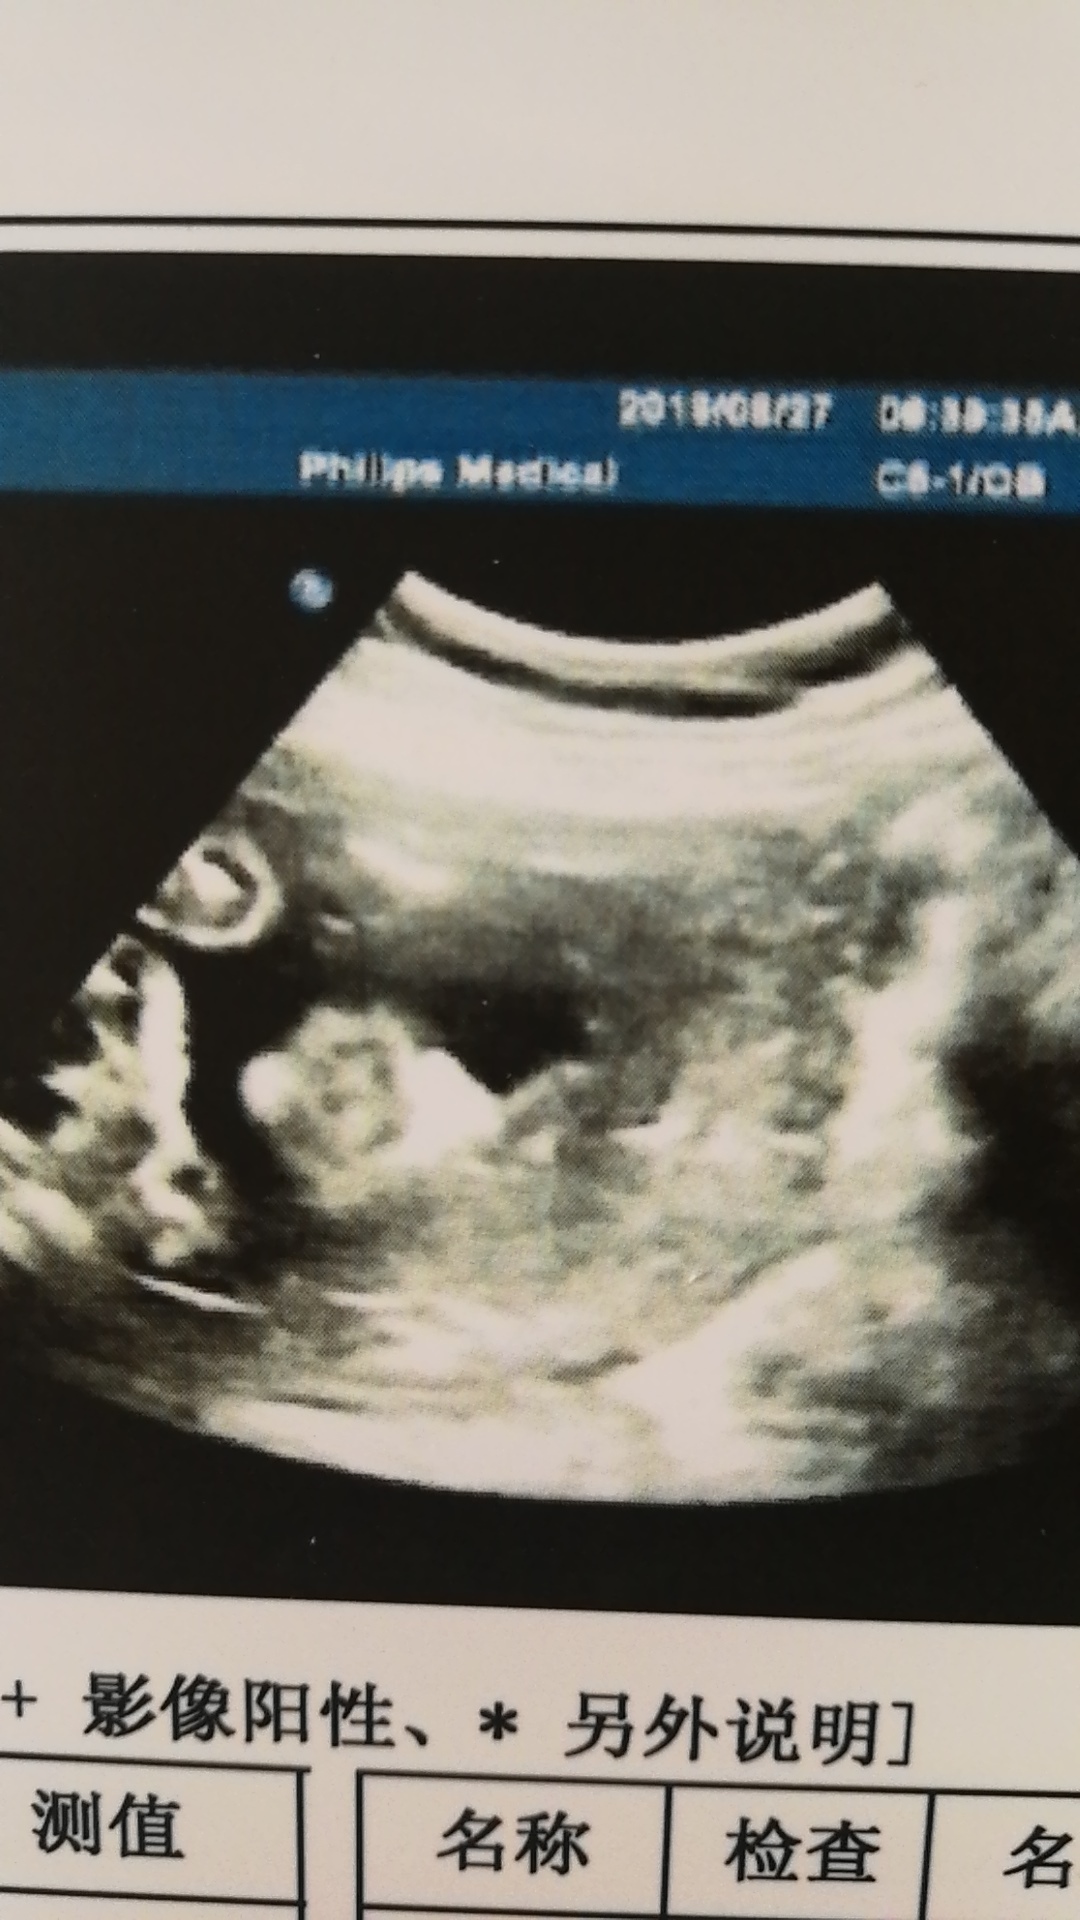

23周大排畸,尿蛋白不合格,是什么原因?是不是补钙补多了?还是憋尿憋的?